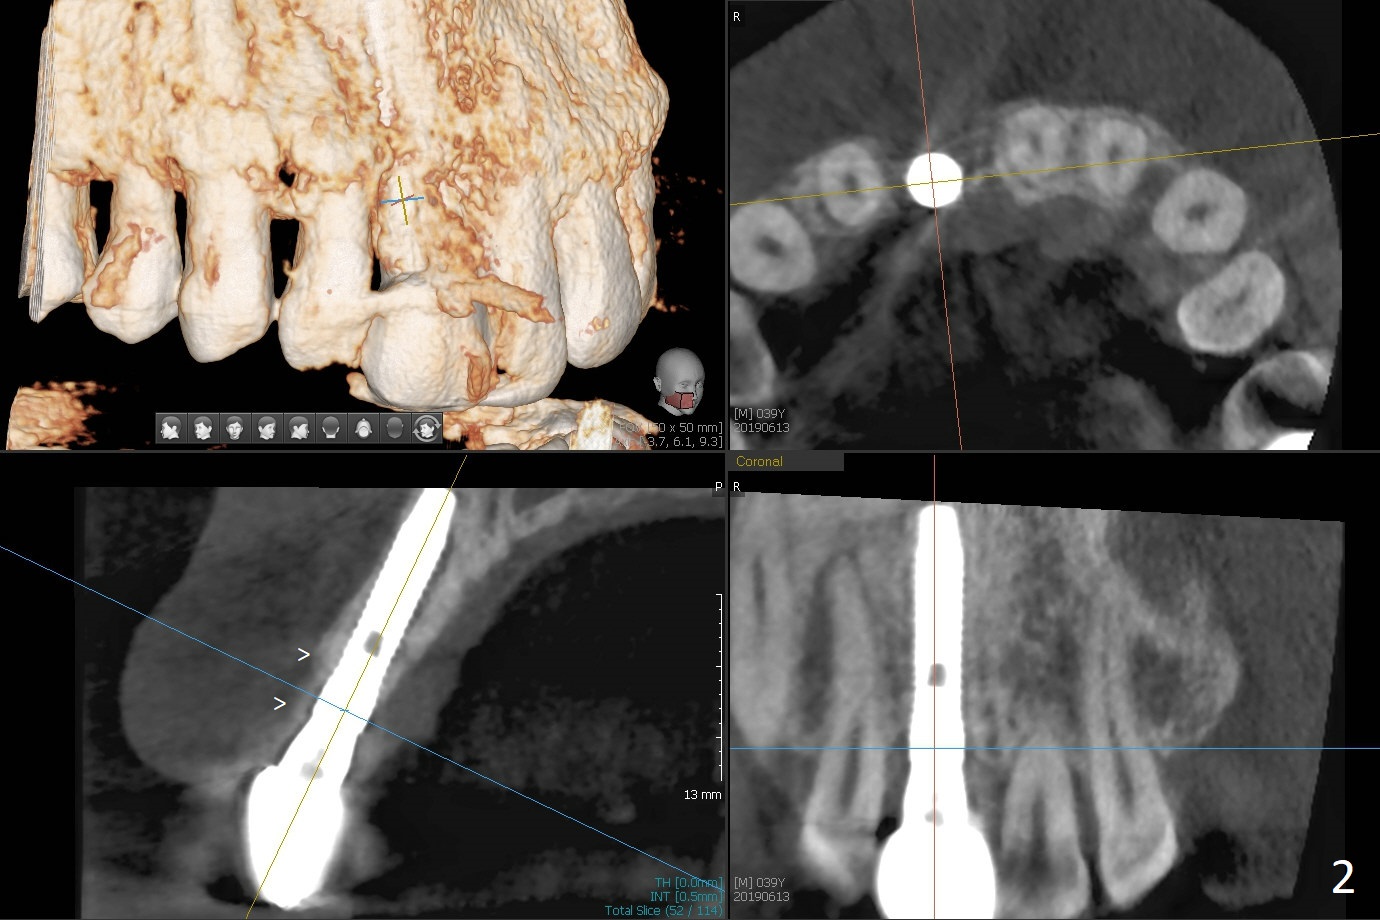

The patient returns because of purulent exudate from the buccal fistula (Fig.1 *) 1 year 9 months postop (1 year 3 months post cementation). Preop CT shows buccal thread exposure (Fig.2 arrowheads). To prevent postop gingival recession, a semilunar incision is made between the fistula and the gingival margin (Fig.3). After removal of granulation tissue (Fig.4), allograft in sticky bone form is packed (Fig.5). Following placement of PRF membrane and 6-month collagen membrane, the wound is closed (Fig.6). Since the implant (Fig.7 I) thread exposure is within bone (B) boundary (Fig.8 red dashed line), bone graft with PRF should be able to take care of periimplantitis (A: abutment). To prevent periimplantitis in similar situation, the immediate implant should be placed deep (not necessarily long, 18 mm) and narrower (3.5 mm instead of 3.8 mm). The defective buccal plate should be repaired with sticky bone and collagen membrane with incision if necessary. The wound does not dehisce 1 week postop (Fig.9) or 3 weeks postop (Fig.10, immediately post suture removal). Although bone graft seems to stay in place 6 months postop (Fig.11,12), the patient complains of bone graft expulsion sometimes. The buccal gingiva has deficiency (Fig.13). To fix it, make a remote incision (Fig.14 black line) and dissect before gingiva graft (Fig.15 dashed line). After removal of crown/abutment, the sinus track and implant surface are treated with Waterlase. A shorter cuff abutment is placed (4.5x5(4 to 3) mm) with a new provisional. The patient feels better with reduced sinus track 2 weeks postop (Fig.16).